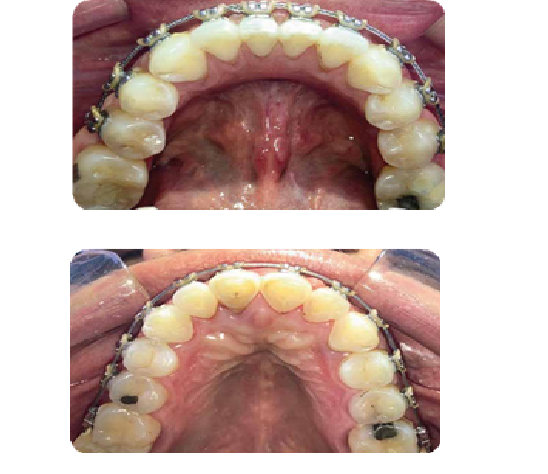

CASO CLÍNICO

Paciente de 13 años de edad acude a consulta por presentar severa apiñación dental y un maxilar pequeño, por lo que optamos por un tratamiento de ortodoncia (brackets), terminando el tratamiento de manera exitosa, luego de ello se procede a realizar mejoras estéticas

con un blanqueamiento dental.